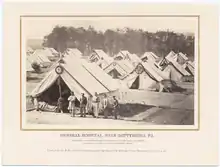

Selected image –

Photo credit: Public domain (U.S. Brookhaven National Laboratory)